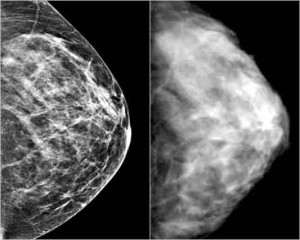

Mammografia e densita’ mammografica: un valido indizio per predire rischi tumori seno

L’evoluzione della densità mammografica è un altro indice che va tenuto in conto, spiega Celine Vachon. della Mayo Clinic, che ha evidenziato come ad una riduzione nel tempo si associ a una riduzione del rischio. Lo studio si è basato sui dati di 1.900 donne sane, età media 35 anni, e 219 colpite dalla malattia. L’esame dei risultati diagnostici effettuati nel corso degli anni ha permesso di stabilire che, tra le donne che avrebbero poi sviluppato il tumore, la densità dei tessuti si era mantenuto costantemente alto nel tempo. Analisi che confortano i medici-senologi nella scelta della mammografia come strumento per monitorare i cambiamenti nel corpo femminile. Tuttavia, come un altro studio presentato durante il Congresso evidenzia, i costi in termini di radiazioni per la diagnosi, soprattutto nelle donne giovani, andrebbe limitata. Obiettivo di una ricerca dell’Università delle Hawaii: trovare alternative tecnologiche innovative, ma meno bio-tossiche per le cellule. (ASCA)